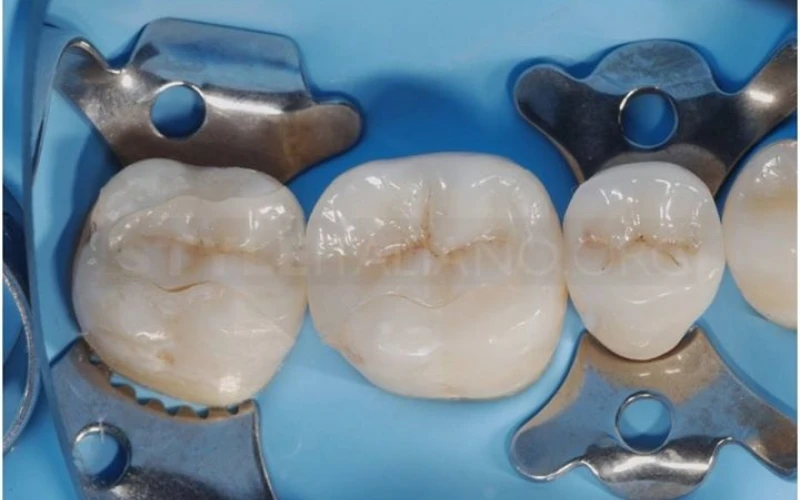

15. Hình ảnh ở buổi hẹn thứ hai. Tháo phục hình tạm (Telio Ivoclar Vivadent), cắt chỉ và đặt đê. Chú ý khả năng mô lành thương chỉ sau 1 tuần.

16. Thử inlay.